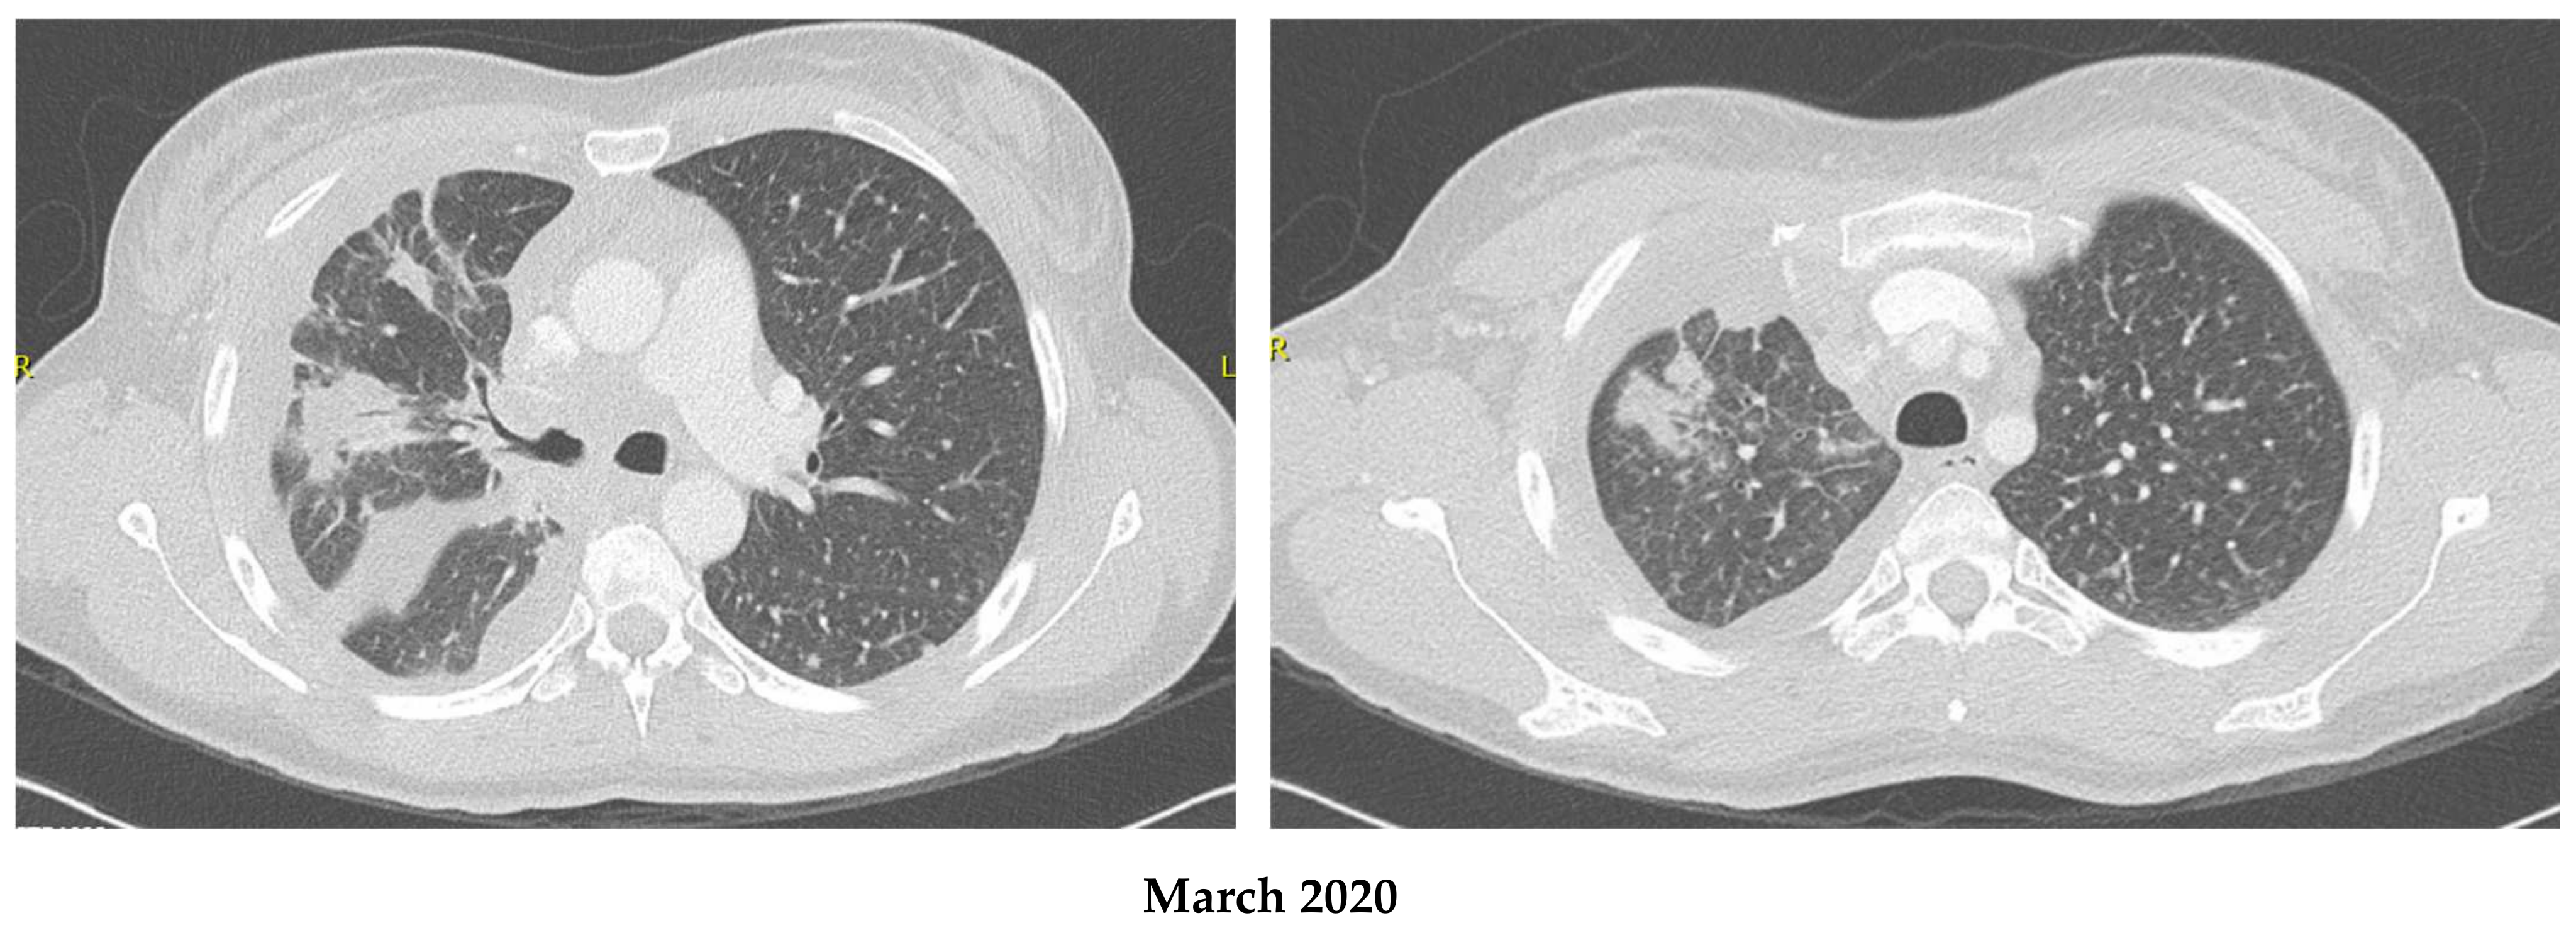

2.1. Patient 1